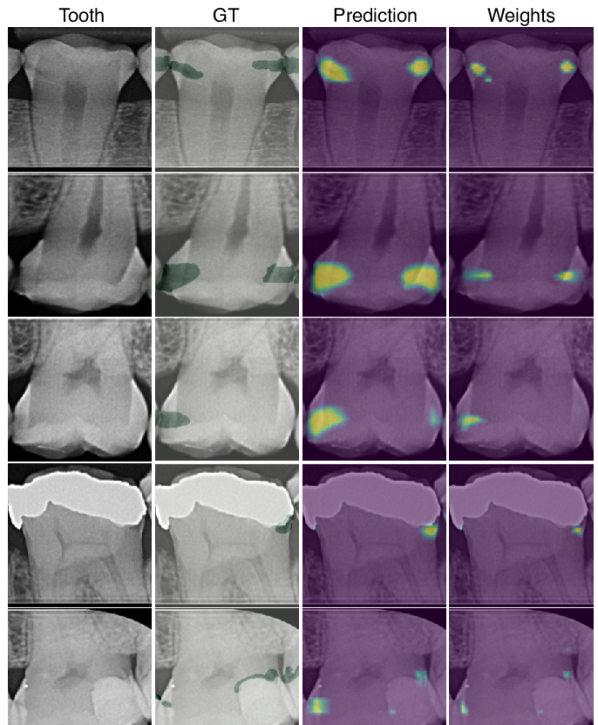

Fig. LABEL:fig:bw shows a positive BWR and EMIL heatmaps. is sensitive and detects all lesions, while is precise and focuses on the most discriminative regions. A colorbar indicates local class probabilities and attention values, respectively. Fig. LABEL:fig:teeth adds a qualitative visualization comparison. Attribution methods such as saliency maps Simonyan et al. (2014), Grad-CAM Selvaraju et al. (2017) or occlusion maps Zeiler and Fergus (2014) (ResNet), as well as DeepMIL, are sensitive to positive cases (rows 1-3) but not precise. Moreover, these methods do not ignore the negative class (row 4), and false negatives are accompanied by false positive visualizations (row 5). This is resolved in Y-Net and EMIL (), and caries may be highlighted although the activation is too low to cross the classification threshold (e.g., row 5, column 8).

Table 4 adds a quantitative comparison where the overlap of ground truth and heatmaps is computed as Intersection over Union (IoU, in %) for the positive class. For a fair comparison, we follow Viviano et al. (2021) and set the topmost pixels of each map to 1, so that the total area equals the respective ground truth. When considering all confidences (IoU@0), Saliency and EMIL localize best. In the interactive settings, scores improve significantly. Y-Net shows high IoU due to its parametrized decoder, which outputs high-res masks. When replacing the decoder by a bilinear upsampler (factor 4) + 1x1 conv output layer (Y-Net-S), results are comparable to EMIL. We also conduct an experiment where only confident predictions () are retained. The localization performance increases most in EMIL models, by 12.4 and 30.9 percentage points.

fig:teeth